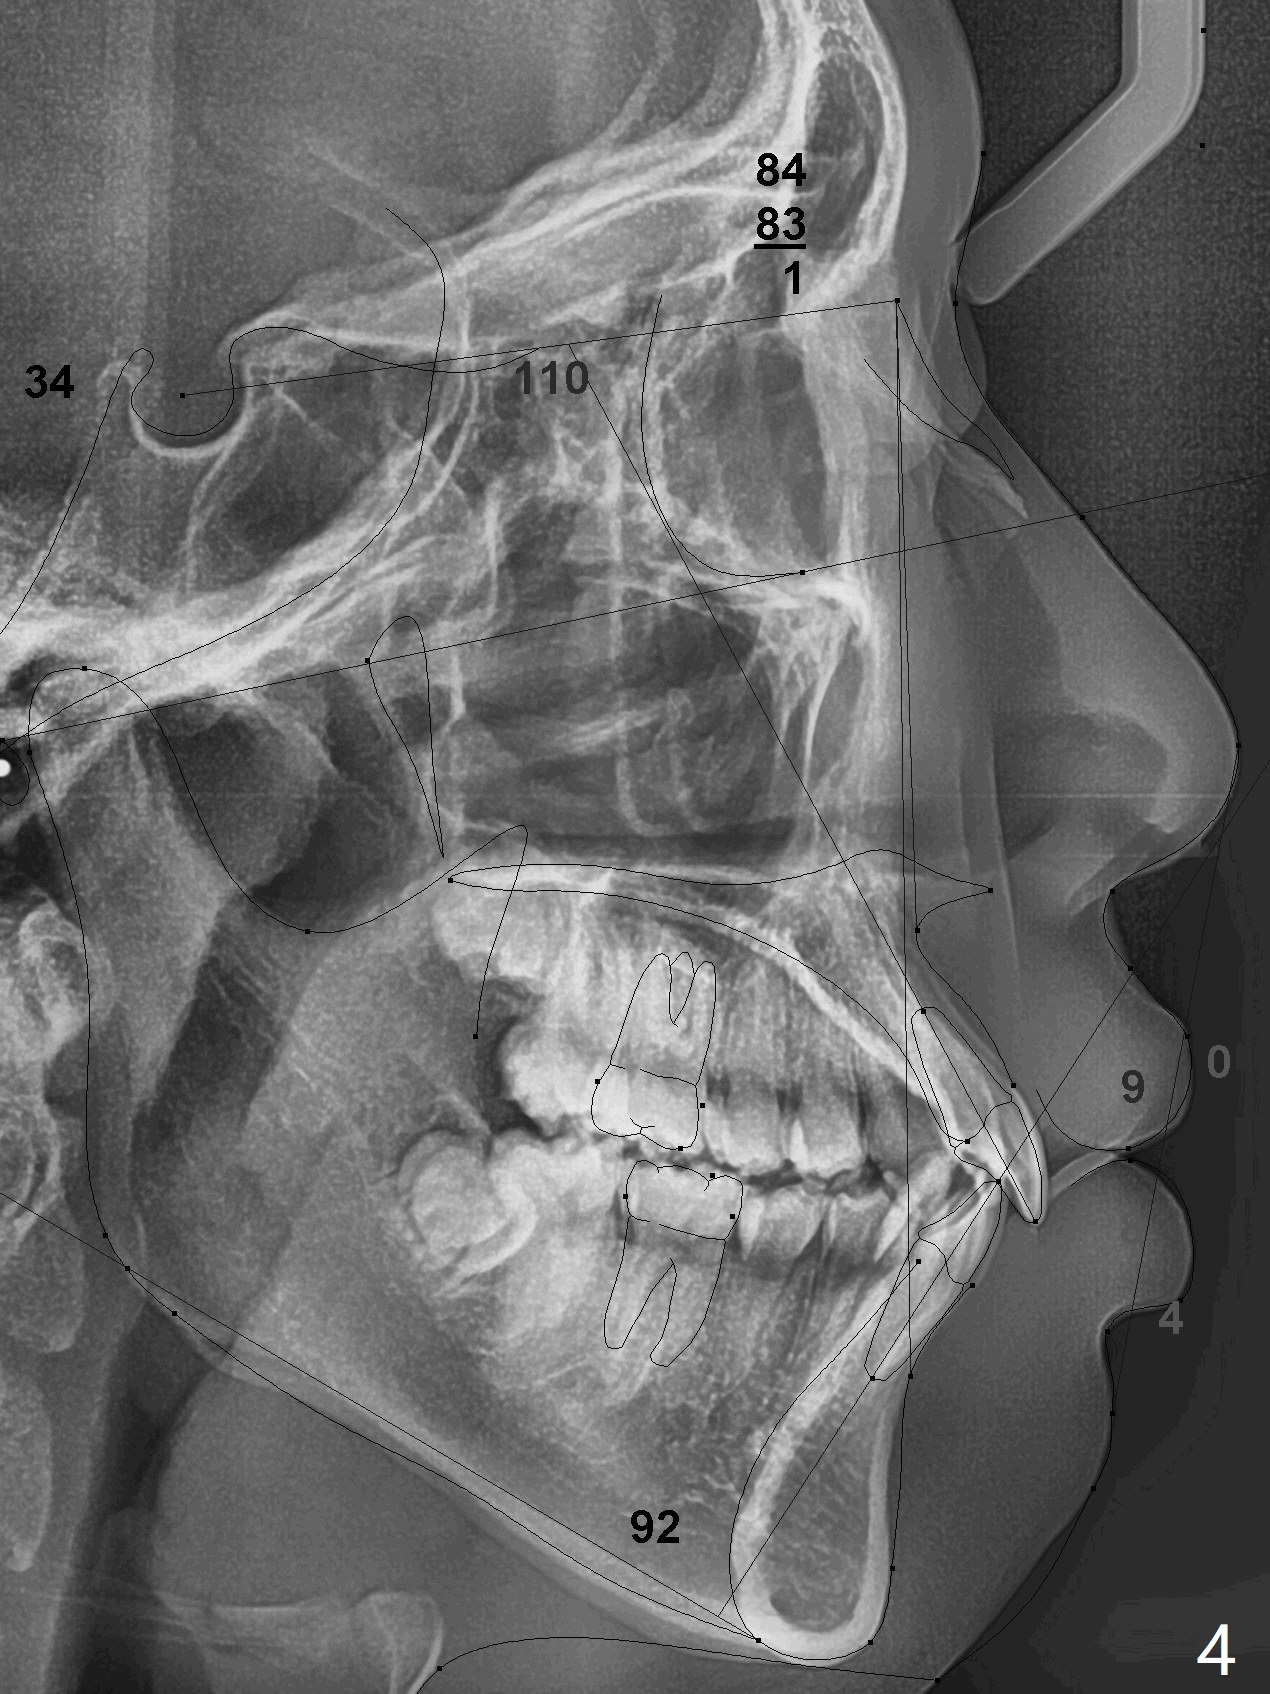

A 15-year-old man requests orthodontic treatment and agrees with extraction.  It appears that the maxilla is more protrusive than the mandible (Fig.1-4, 6,8).  The lower right canine has severe gingival recession (Fig.6,7,10).  Can we extract U4s and LR3 or 2 instead, considering relatively normal alignment in LL (Fig.8, occlusal view)?